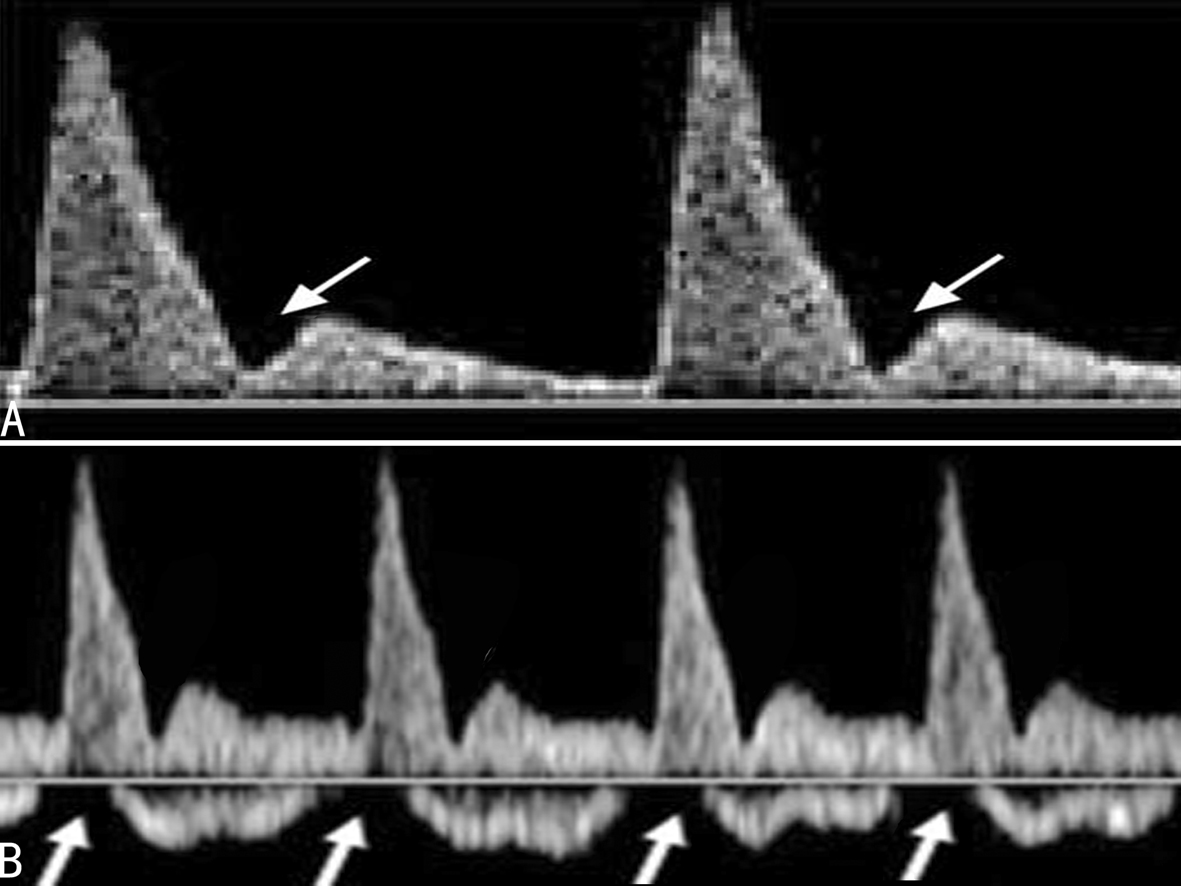

正常妊娠时胎儿大脑中动脉血流S/D、PI、RI随妊娠周数的增加呈下降趋势,以保证为脑组织发育提供足够的氧气。胎儿缺氧时,脑保护效应机制启动,血流重新分配,脑动脉血流阻力进一步降低,脑组织供血得到保障;多普勒超声检查可以发现大脑中动脉血流速度增加,尤其是舒张期血流速度增加的更为明显,S/D、PI、RI的降低(图3)。由此导致的结果是脑血流量明显增加。当S/D<4.0时则提示胎儿缺氧,S/D越低胎儿缺氧越严重。PI和RI的改变可能先于血流峰值速度的改变,

图3 MCA血流速度曲线显示舒张期血流B图>A图